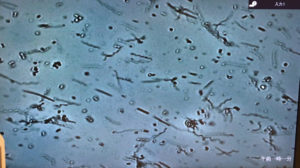

岩崎歯科では位相差顕微鏡を使ってお口の中にいる細菌を見ることができます👀

—お口の中は細菌がいっぱい—

大人のお口の中には、300〜700種類の細菌が生息していると言われています😵

歯をしっかりと磨く方で1000〜2000億個、ほとんど磨かない方は1兆個もの細菌が住み着いています😵

こちは顕微鏡で見える細菌です。

肉眼では見ることができない細菌です。

4000倍に拡大したものです。

腸内環境と同じで善玉菌と悪玉菌のように、お口の中も良い菌、悪い菌がいるのです。

びっくりしないでください!!誰のお口の中にも生息しています。大切なのは、細菌のバランス、種類なのです。